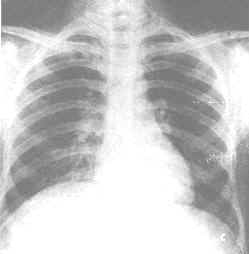

5.異位損害 指蟲卵和(或)成蟲寄生在門靜脈系統之外的器官病變。以肺與腦較為多見。肺部病變為間質性蟲卵肉芽腫伴周圍肺泡炎性浸潤, 腦部病以頂葉與顳葉的蟲卵肉芽腫為多,多發生在感染後6個月~1年。

2.CT掃描 晚期血吸蟲病患者肝包膜與肝內門靜脈區常有鈣化現象,CT掃描可顯示:肝包膜增厚鈣化等特異圖像。重度肝纖維化可表現為龜背樣圖像。